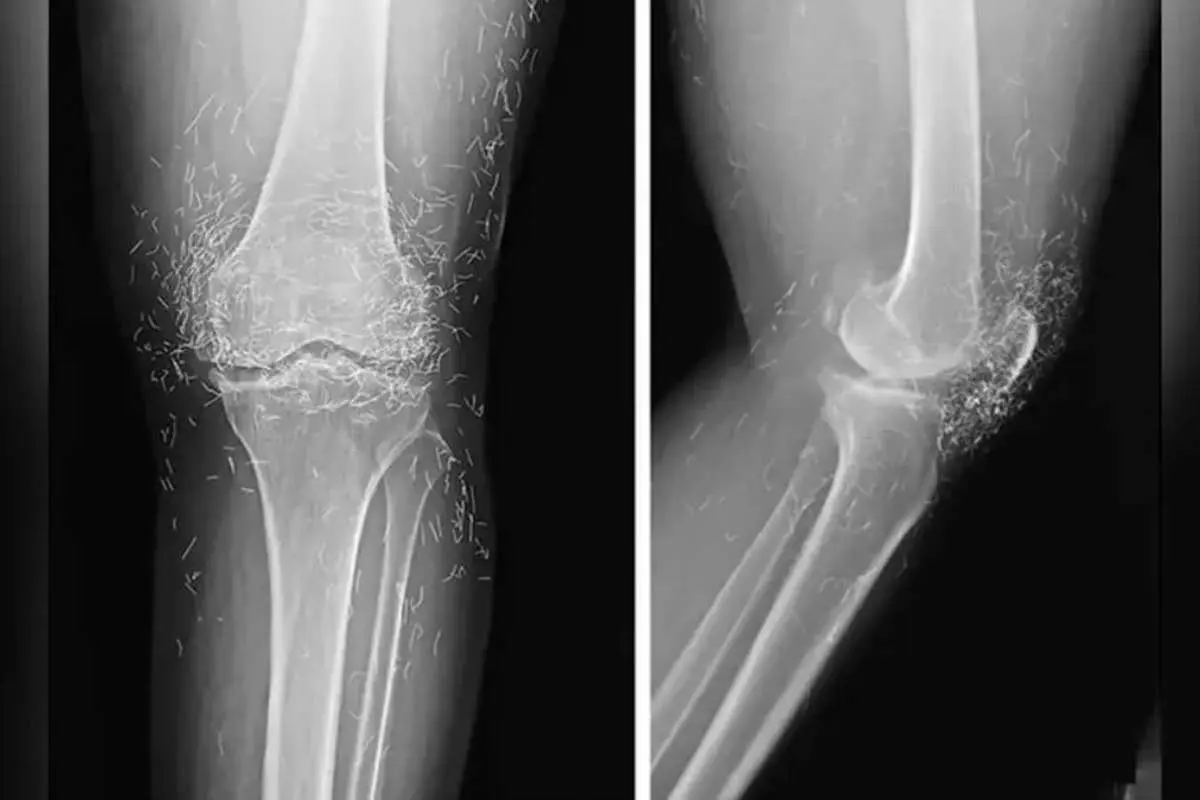

پزشکان کره جنوبی، صدها رشته‌ نازک از طلای خالص در زانوهای زن ۶۵‌ساله مبتلا به آرتروز پیدا کردند.

در یک مورد نادر پزشکی در کره جنوبی، پزشکان هنگام درمان درد و خشکی شدید زانوهای زنی که به آرتروز مبتلا بود، متوجه وجود صدها رشته طلای خالص در بافت‌های اطراف زانوهای او و البته دست‌هایش شدند.

اما این روش هم نه‌تنها دردی از این زن دوا نکرد، بلکه زانودرد او را هم شدت بخشید. درنهایت او مجبور شد دوباره به بیمارستان مراجعه کند و پزشکان هنگام تصویربرداری از زانوها و دست‌های او متوجه صدها رشته‌ ریز و نازک از طلا در بافت‌های اطراف زانو و دست‌های این زن شدند.